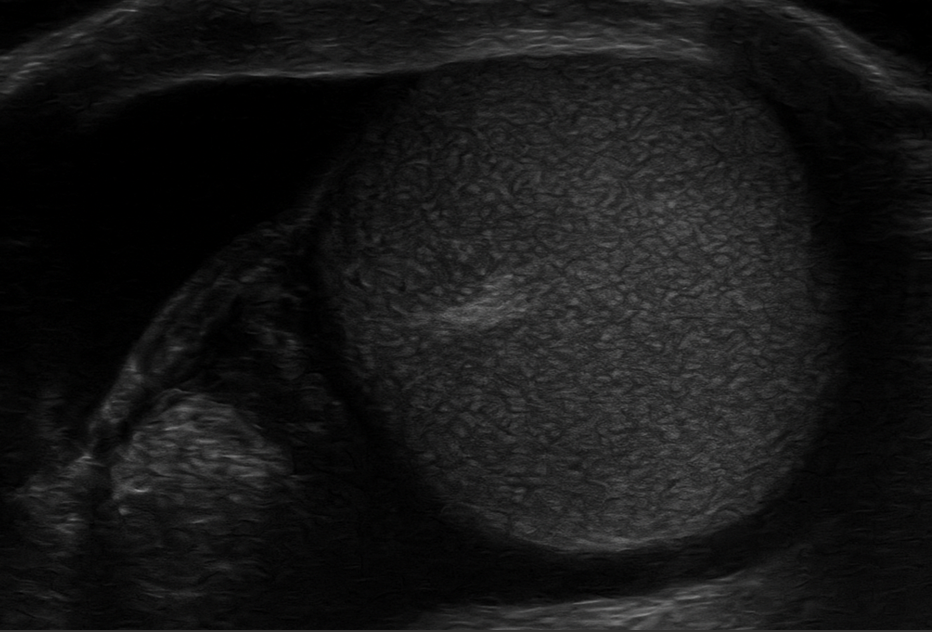

Ante la sospecha de torsión testicular, se realiza una ecografía escrotal con sonda lineal de alta frecuencia por el médico de familia en el centro de salud observándose un testículo derecho aumentado de tamaño, con ecogenicidad heterogénea y ausencia total de flujo en el estudio Doppler. Se observó también aspecto arremolinado del cordón espermático (signo del remolino), hallazgo compatible con torsión testicular aguda. La ecografía del testículo izquierdo fue normal, con flujo conservado.

Torsión testicular derecha confirmada por ecografía clínica.